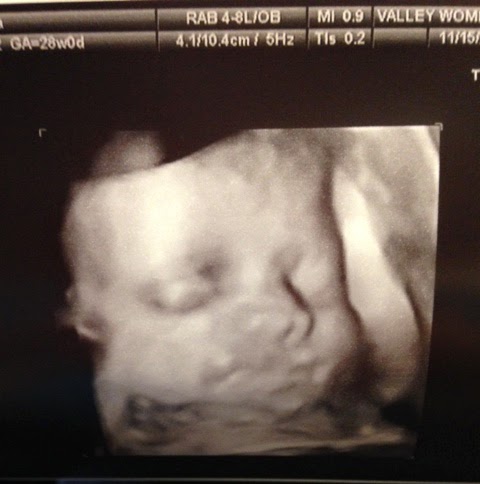

While we were looking around in there, our baby boy showed a little of his personality, knocking right back at the ultrasound tech with his tiny balled up fists, and even smiling a little, which we tried to catch in this 3-d image. Seeing his face for the first time only makes me want to meet him sooner, but we’ll let him cook a little while longer.